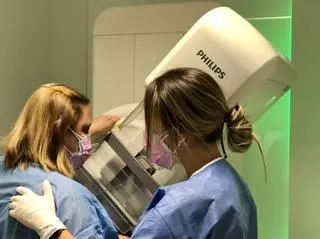

Sanidad anima a las mujeres a que se incorporen al programa de cribado con mamografías desde los 45 años

Coincidiendo con el Día Internacional contra el Cáncer de Mama, el conseller de Sanidad, Marciano Gómez, ha recordado que el programa de prevención de la Comunidad Valenciana tiene más de 30 años de actividad desde su puesta en marcha en 1992 y fue el segundo en implantarse en toda España. En estas tres décadas, "se han podido detectar 24.000 cánceres de mama y se han realizado más de cinco millones de mamografías gracias al programa".

"Tras 30 años de funcionamiento del programa y los buenos resultados tanto en supervivencia como en calidad de vida, animo a todas las mujeres a que se incorporen a los planes de cribado, ya que la promoción y la prevención de la salud cura", ha destacado Gómez.

El programa tiene como objetivo principal la reducción de la mortalidad por este cáncer a través de la detección precoz de lesiones que aún no han manifestado síntomas y, por tanto, son susceptibles de tratamientos más conservadores, con menos efectos secundarios y acompañados de un mayor aumento de la supervivencia de las mujeres.

A través de estas unidades, 800.000 mujeres de la Comunidad Valenciana de entre 45 y a 69 años, son citadas cada dos años para la realización de un estudio mamográfico bilateral.

Un aparato para hacer mamografías en la Sanidad pública / INFORMACIÓN